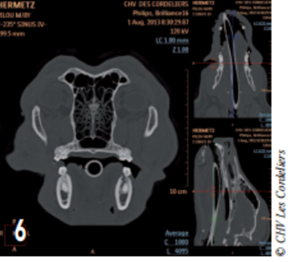

L’améloblastome acanthomateux étant une tumeur localement agressive, un bilan d’extension par scanner a été réalisé.

Le scanner a révélé la présence d’une lyse osseuse de l’os alvéolaire mandibulaire s’étendant de la racine dorsale de la carnassière jusqu’à la racine caudale de la deuxième prémolaire (photos 2 à 6).

Photo 6 : La lyse osseuse est visible au niveau de la deuxième molaire.